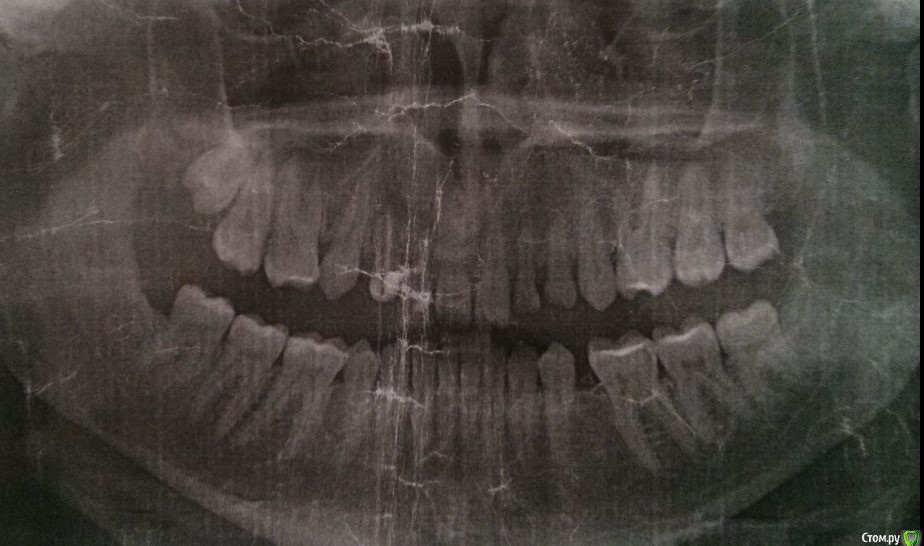

adentiyaHelp Опубликовано 29 марта, 2018 Автор Поделиться Опубликовано 29 марта, 2018 (изменено) Жалобы: проблемы с пережевыванием пищи, нет зуба в переди - как ходить - просто очень комплексую.Провел ортодонтическое лечение на нижней челюсти, поставил 2 импланта. Как протезировать дальше?Снимок 2018, после ортодонтического лечения нижней челюсти: http://prntscr.com/ixzbdh Изменено 29 марта, 2018 пользователем adentiyaHelp Ссылка на комментарий